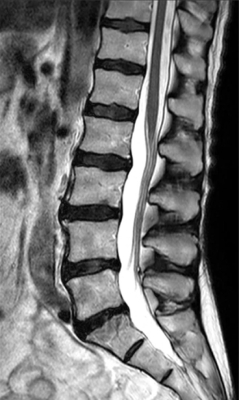

T2w TSE

Ingenia Ambition 1.5T